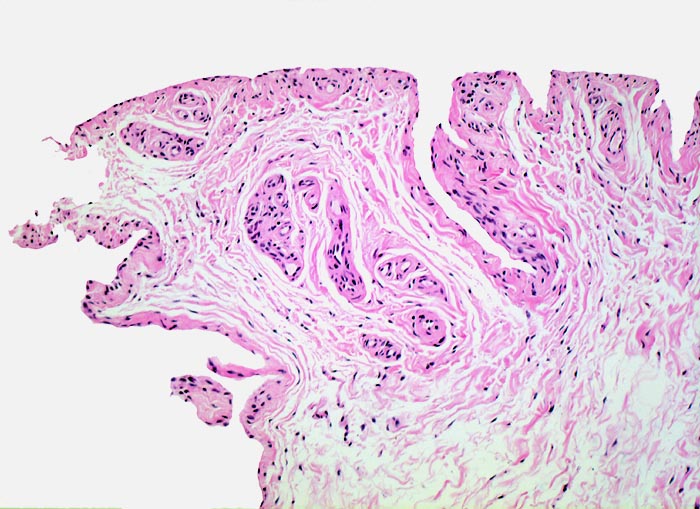

In Abhängigkeit von der Entzündungsdauer werden unterschiedliche morphologische Befunde beschrieben. Die initiale proliferative Phase ist charakterisiert durch eine Hyperplasie der Synovialis, Fibrinexsudate und Gelenkergüsse. In der destruktiven Phase kommt es zur Zerstörung von Gelenkknorpel und gelenknahem Knochen durch Ausbildung eines intraartikulären Pannusgewebes (> 194). Die ausgebrannte Phase ist gekennzeichnet durch eine synoviale Fibrose mit zunehmender Ankylose (= Gelenkversteifung).

Das gelenkauskleidende Gewebe, die Auskleidung von Sehnenscheiden und Bursae nennt man Synovialis. Die Gelenkflüssigkeit heisst Synovia. Die auskleidenden synovialen Deckzellen sind mesenchymale, keine epithelialen Zellen.

Normalbefund